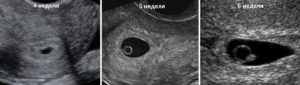

УЗИ 3 недели

УЗИ 4 недели

Как же выглядит эмбрион в самом начале своей жизни и какой размер плодного яйца считается нормой в первом триместре?

| 3-4-я | Средний внутренний диаметр плодного яйца – 15 мм, стенки матки утолщаются. |

| 5-я | СВД уже 18 мм. Яйцо вытягивается, становится удлиненной формы и заполняет всю полость матки. Начинает формироваться сердечно-сосудистая система малыша. В этот период врач после ультразвука обычно уже может подтвердить зачатие. |

| 6-я | СВД уже 21 мм, КТР – от 6 мм, можно легко услышать сердцебиение. |

| 7-я | Показатели СВД И КТР – 23-24 и 10-11 мм соответственно. На мониторе видно овально-удлиненное плодное яйцо, легко проследить его движение и прикрепление плаценты. |